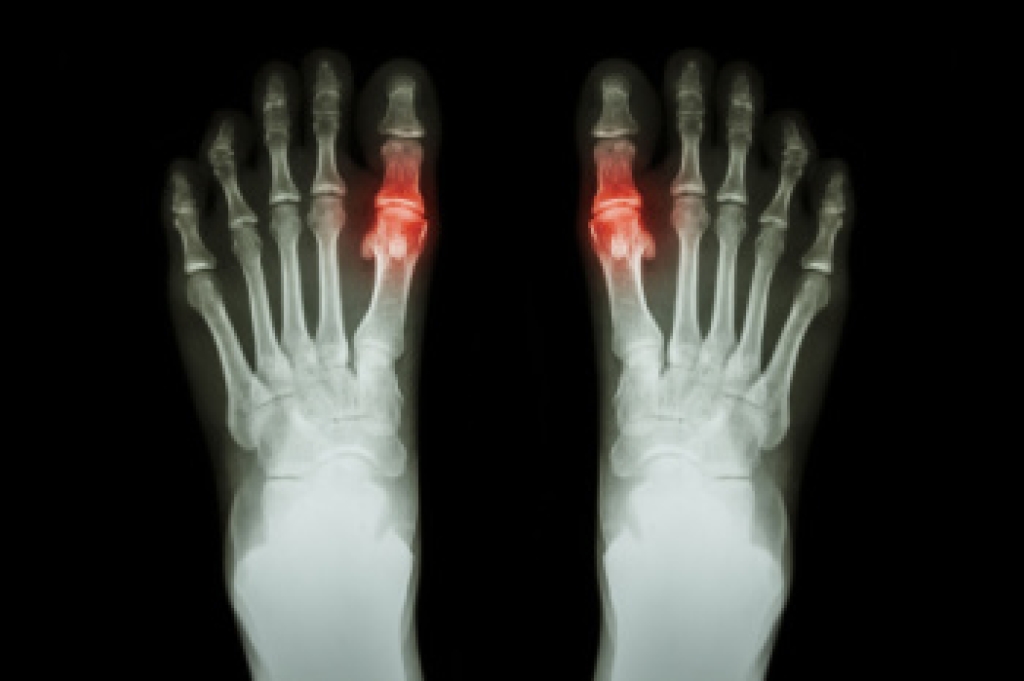

Middle-toe joint pain can result from various factors, often affecting daily activities and mobility. One common cause is arthritis, which leads to inflammation and stiffness in the joint. This condition can be a result of wear and tear over time or due to an autoimmune disorder. Another cause of this type of pain is a bunion, where a bony bump forms at the base of the big toe, as the result of misalignment of the toes. Trauma or injury, such as a sprain or fracture, can also lead to pain in the middle toe joint. Symptoms of middle toe joint pain include swelling, redness, and tenderness in the affected area. The pain typically worsens with movement, and it may become difficult to walk or wear shoes. In some cases, the joint may become stiff, limiting flexibility. If you have toe pain, it is suggested that you schedule an appointment with a podiatrist who can determine what the cause is, and offer viable treatment solutions.

In many cases the cause of toe pain is obvious, but in others, a podiatrist may want to use more advanced methods to determine the problem. These can range from simple visual inspections and sensation tests to X-rays and MRI scans. Prior medical history, family medical history, and any recent physical traumatic events will all be taken into consideration for a proper diagnosis.